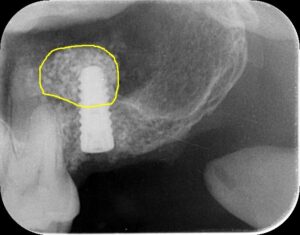

本日は腫れないサイナスリフト ラテラルスリット法を行いました

アテラルスリットは、笹尾歯科医院オリジナルオペ手法です。

治療で得られるメリット 奥歯にインプラントを埋入することができる

ラテラルウィンドウ法に比べ切開部位が少なく侵襲が少ない

ソケットリフト法に比べ、槌打の不快がなく、膜の損傷のリスクが少ない

治療の際に起こるリスク・副作用 シュナイダー膜の損傷・通常の外科に伴うリスク